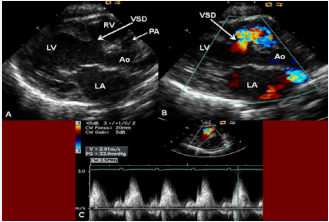

Figure 7 Selected video frames from parasternal long axis views of a neonate with tricuspid atresia with normally related great arteries demonstrating enlarged left atrium (LA) and left ventricle (LV), a small right ventricle (RV), and a moderate-sized ventricular septal defect (VSD; thick arrow) on 2D (A) and color flow (B) imaging. Turbulent flow (B) with a Doppler flow velocity of 2.91 m/s by continuous wave Doppler (C) suggests some restriction of the VSD. Ao, Aorta; PA, pulmonary artery [36].

Figure 7: Selected video frames from parasternal long axis views of a neonate with tricuspid atresia with normally related great arteries demonstrating enlarged left atrium (LA) and left ventricle (LV), a small right ventricle (RV), and a moderate-sized ventricular septal defect (VSD; thick arrow) on 2D (A) and color flow (B) imaging. Turbulent flow (B) with a Doppler flow velocity of 2.91 m/s by continuous wave Doppler (C) suggests some restriction of the VSD. Ao, Aorta; PA, pulmonary artery [36].

The VSD can be demonstrated by 2D (Figure 7A) and the shunt across it by color (Figure 7B), pulsed, and continuous wave (CW) (Figure 7C) Doppler. The peak Doppler flow velocity across the right ventricular outflow tract (RVOT) and pulmonary valve will help in identifying obstruction across these sites. The Doppler data from the VSD and RVOT are helpful in the estimating of pulmonary artery pressures.

As mentioned in a preceding section (Table 1), tricuspid atresia is classified based on the relationship of the great arteries; the most common forms are: Type I, normally related great arteries, and Type II, d-transposition of the great arteries. The great artery relationship is established by following the vessel until bifurcation (Figure 8) or aortic arch. In babies with normally related great arteries the VSD provides blood flow into the lungs. In babies with associated transposition, the VSD provides systemic flow. The VSD may be small, causing obstruction to systemic flow and, therefore, the VSD size should be assessed by 2D (Figures 5, 7A, & 8A) and color (Figures 7B & 9), pulsed (Figure 10), and CW Doppler as necessary.

In Type I (normally related great arteries) patients, the VSD peak Doppler velocity is helpful in estimating the size of the VSD; the higher the velocity, the smaller is the VSD. The RV and pulmonary arterial (PA) pressure may also be estimated using the modified Bernoulli equation:

RV/PA systolic pressure = systolic BP - 4V^2

where RV is the right ventricle, PA is the pulmonary artery, BP is the arm blood pressure, and V is the VSD peak Doppler velocity.